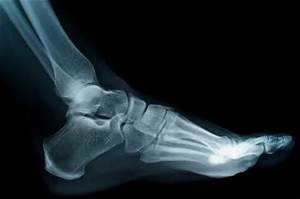

In an effort to provide required training for podiatric medical assistants who perform podiatric radiological procedures in the podiatric office, this online course was developed by TPMA to better train the office staff and to save the doctors money in travel and related costs.

Who Is It For? Any person performing Podiatric (i.e. Foot/Ankle) radiological procedures in the practice of a licensed Podiatric Physician (other than the Podiatric Physician or a Non-Certified Technician (NCT) registered with the Texas Medical Board) must be registered with TDLR as a Podiatric Medical Radiological Technician.